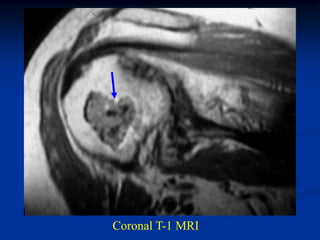

Case #554.1           Enchondroma and ganglion cyst

47 year male with shoulder pain for 6 months

ganglion

enchondroma                cyst

Coronal T-2 MRI

Sagittal T-2 enchondroma   Sagittal T-2 ganglion

Two different T-2 axial cuts showing the enchondroma

and the right cut shows the ganglion